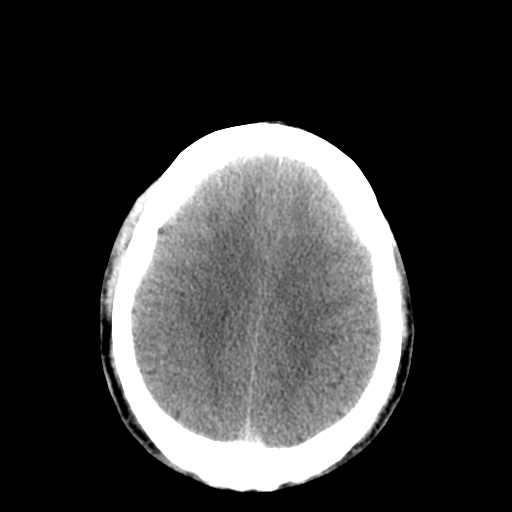

以下是引用李衡钧在2008-9-18 17:37:00的发言:[br]脑质内见两个低密度灶,其内见点状高密度。[br]考虑脑囊虫。建议增强或进一步检查确诊。

以下是引用chmh在2008-9-18 18:45:00的发言:[br]考虑脑囊虫病可能性大,建议行ct增强检查及血清和脑脊液囊虫补体结合试验.